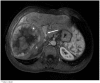

Case presentation: In this case study, we describe a 34-year-old Caucasian man who presented with a large hepatocellular carcinoma in the presence of an Abernethy malformation, which was complicated by the development of pulmonary arterial hypertension.